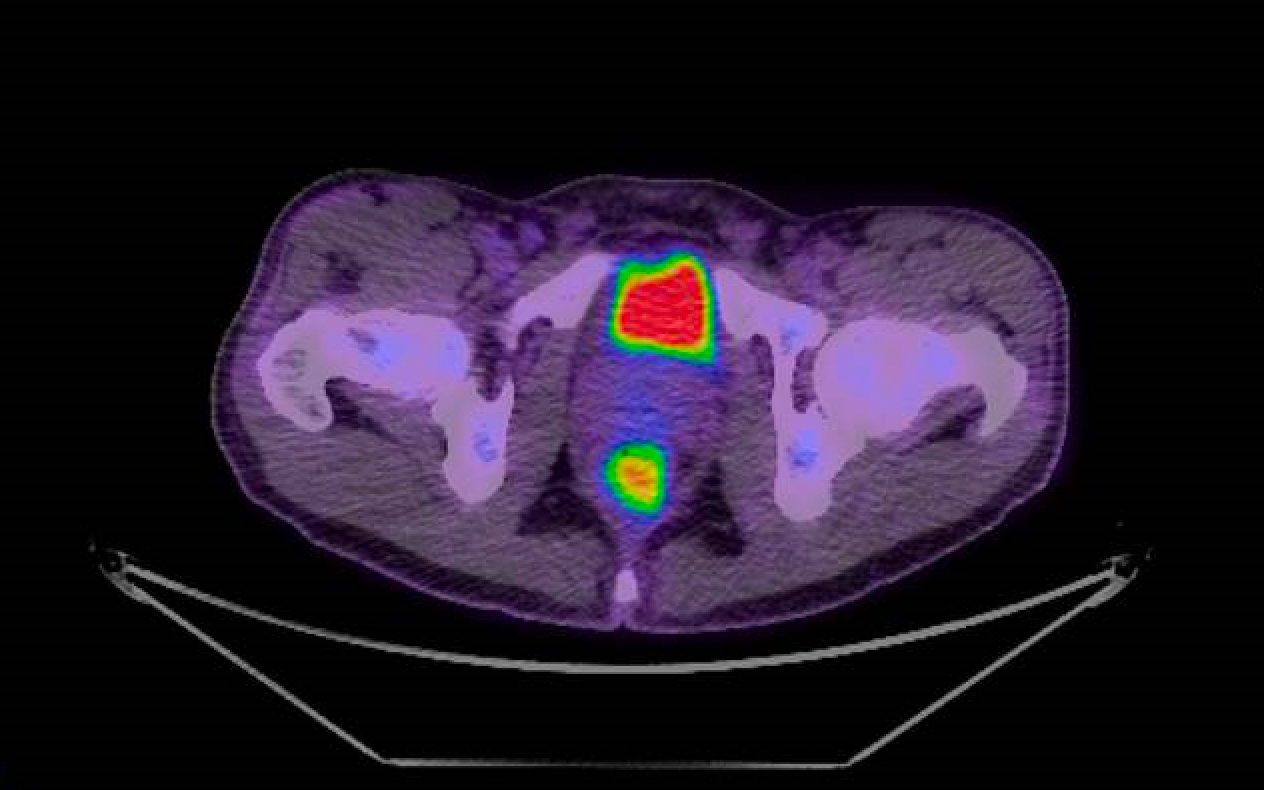

PET scan of the rectum showing site of infection as the lower orange spot. Source: Peter MacCallum Cancer Centre

A combination FDG-PET/CT scan is a combined positron emission tomography (PET) scan which produces images of how organs or tissues inside the body use sugar, a key fuel for the body's organs, with a computed tomography (CT) scan which provides more anatomical information. FDG, or fluorodeoxyglucose, is the sugar compound used as the radioactive tracer in the PET scan.